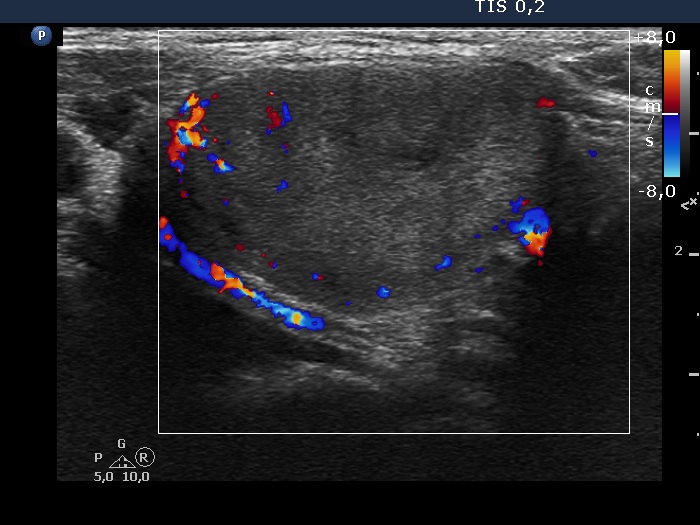

Lower part of the left lobe, transverse scan, color Doppler mode. The nodule presents signs of perilesional blood flow.